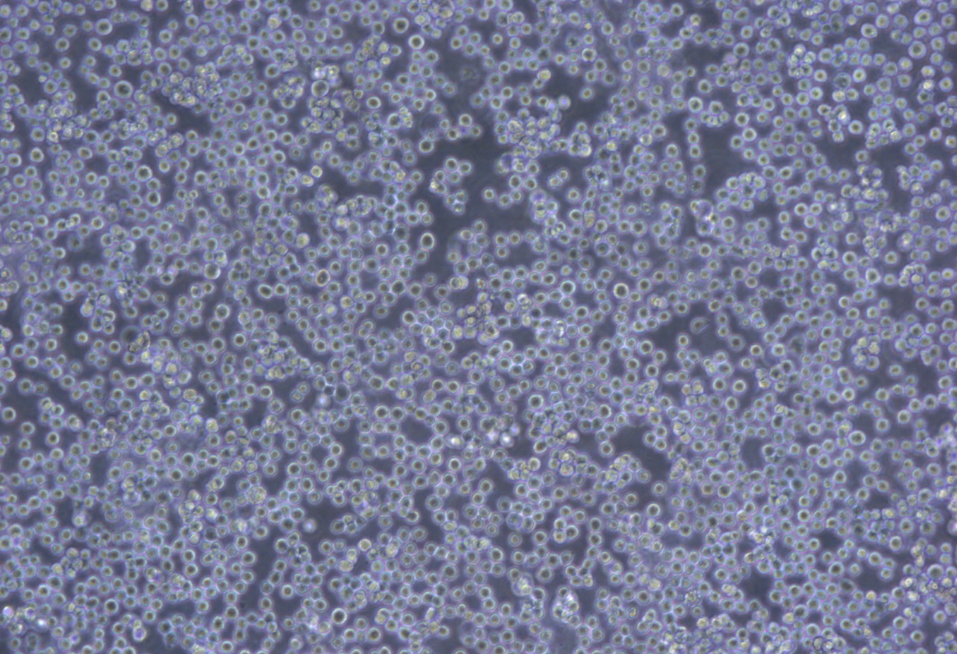

形态 |

淋巴细胞样 |

生长特征 |

悬浮生长 |